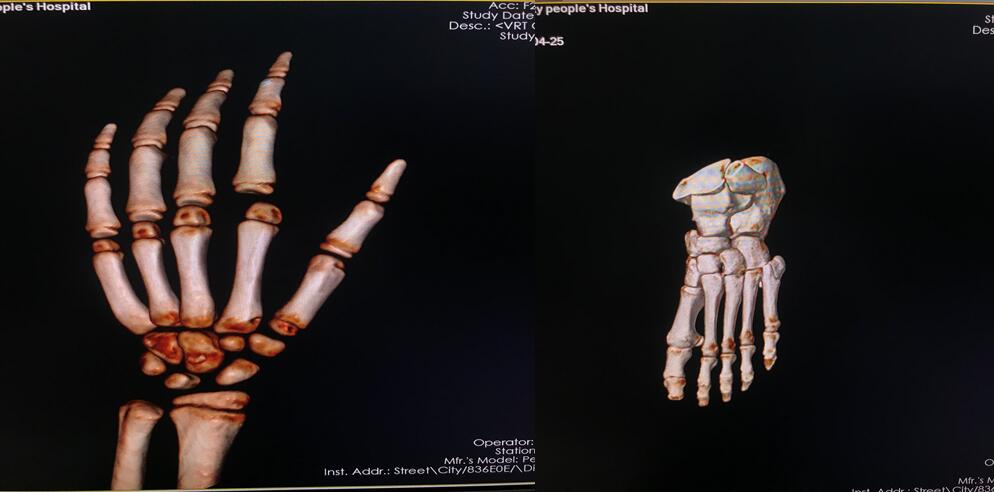

四、开展项目:科室现常规开展全身各部位CT平扫及增强检查、CT三维重建、CT血管造影(CTA、CTV)、(包括冠状动脉CTA)、CT尿路造影(CTU)、全身各部位DR摄片检查、床边摄片、同时开展胆系T管造影、CT定位下穿刺活检。

全身部位三维重建

全身骨三维重建